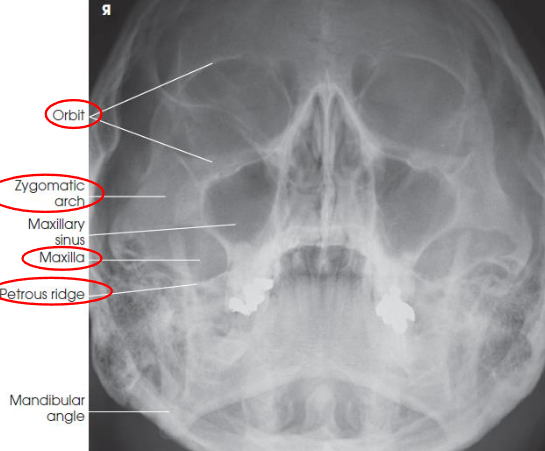

Parietoacanthial (Waters) facial bones image criteria

shows orbits, maxillae, and zygomatic arches

entire orbits and facial bones

no rotation or tilt:

distances between the lateral borders of the skull and the orbits

MSP of head aligned with long axis of collimated field

petrous ridges projected just below maxillary sinuses